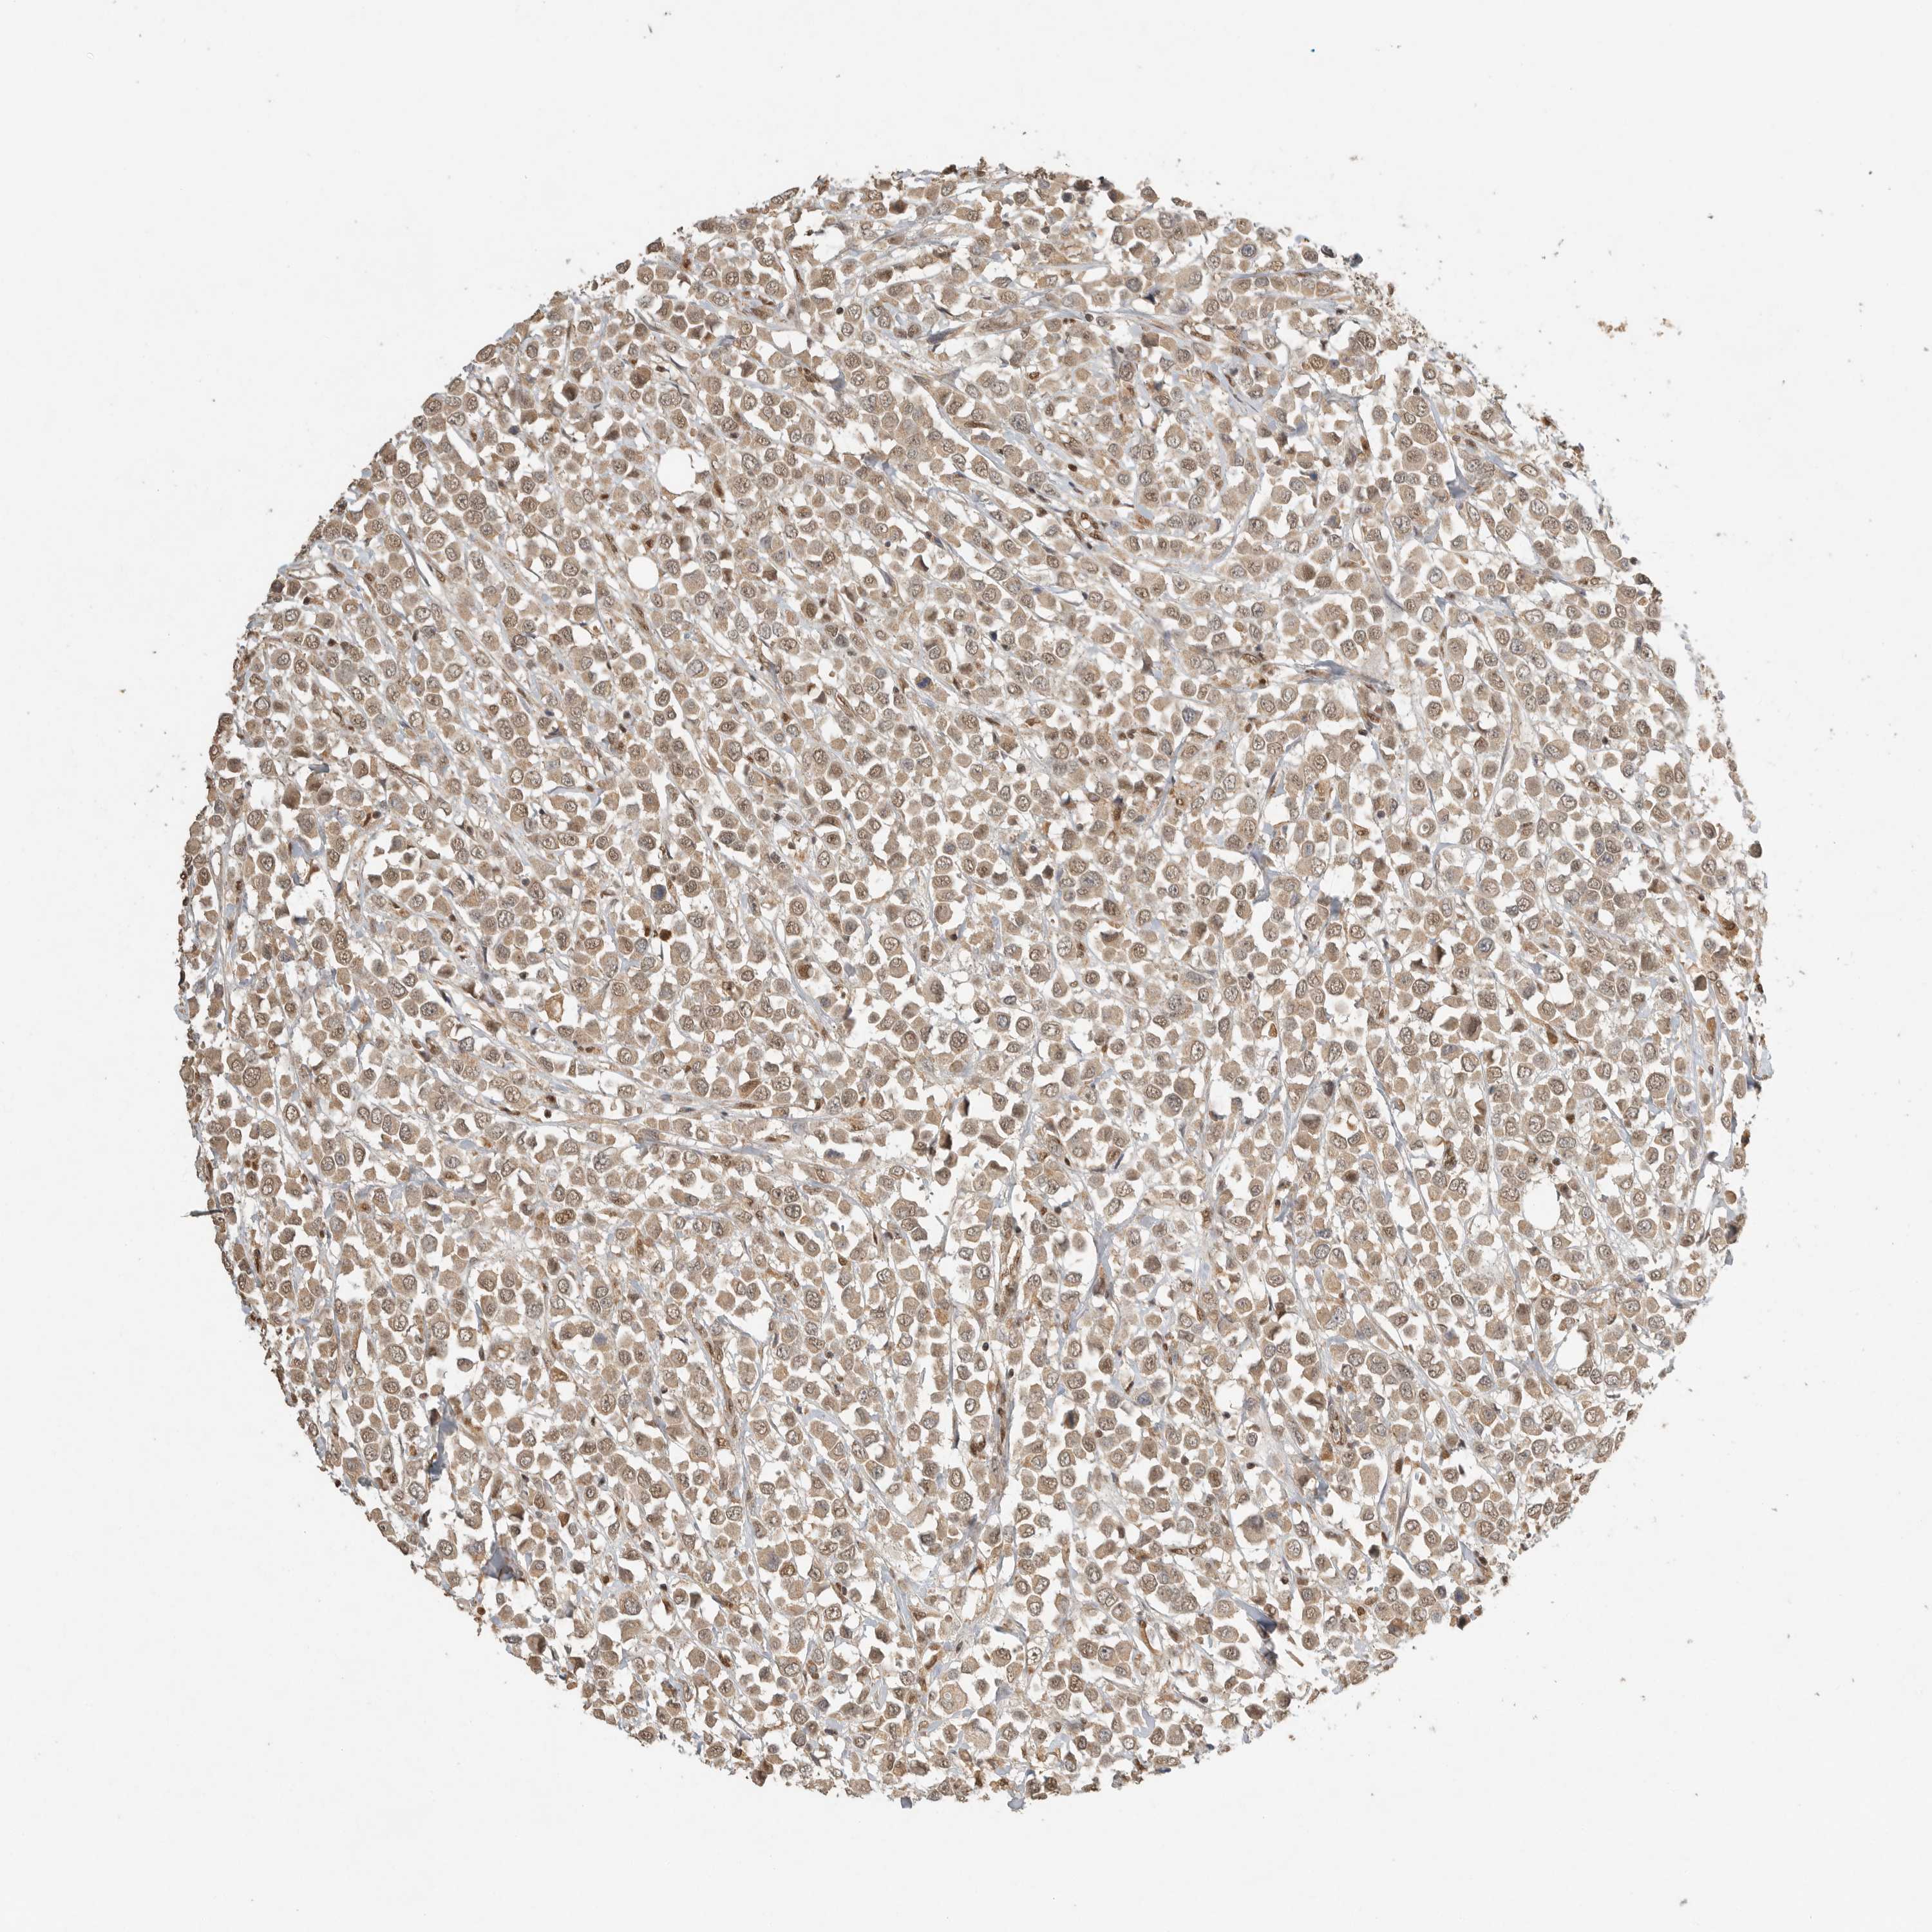

CANCER BREAST CANCER Show tissue menu

BRCA TCGA BRCA VALIDATION PROTEIN EXPRESSION